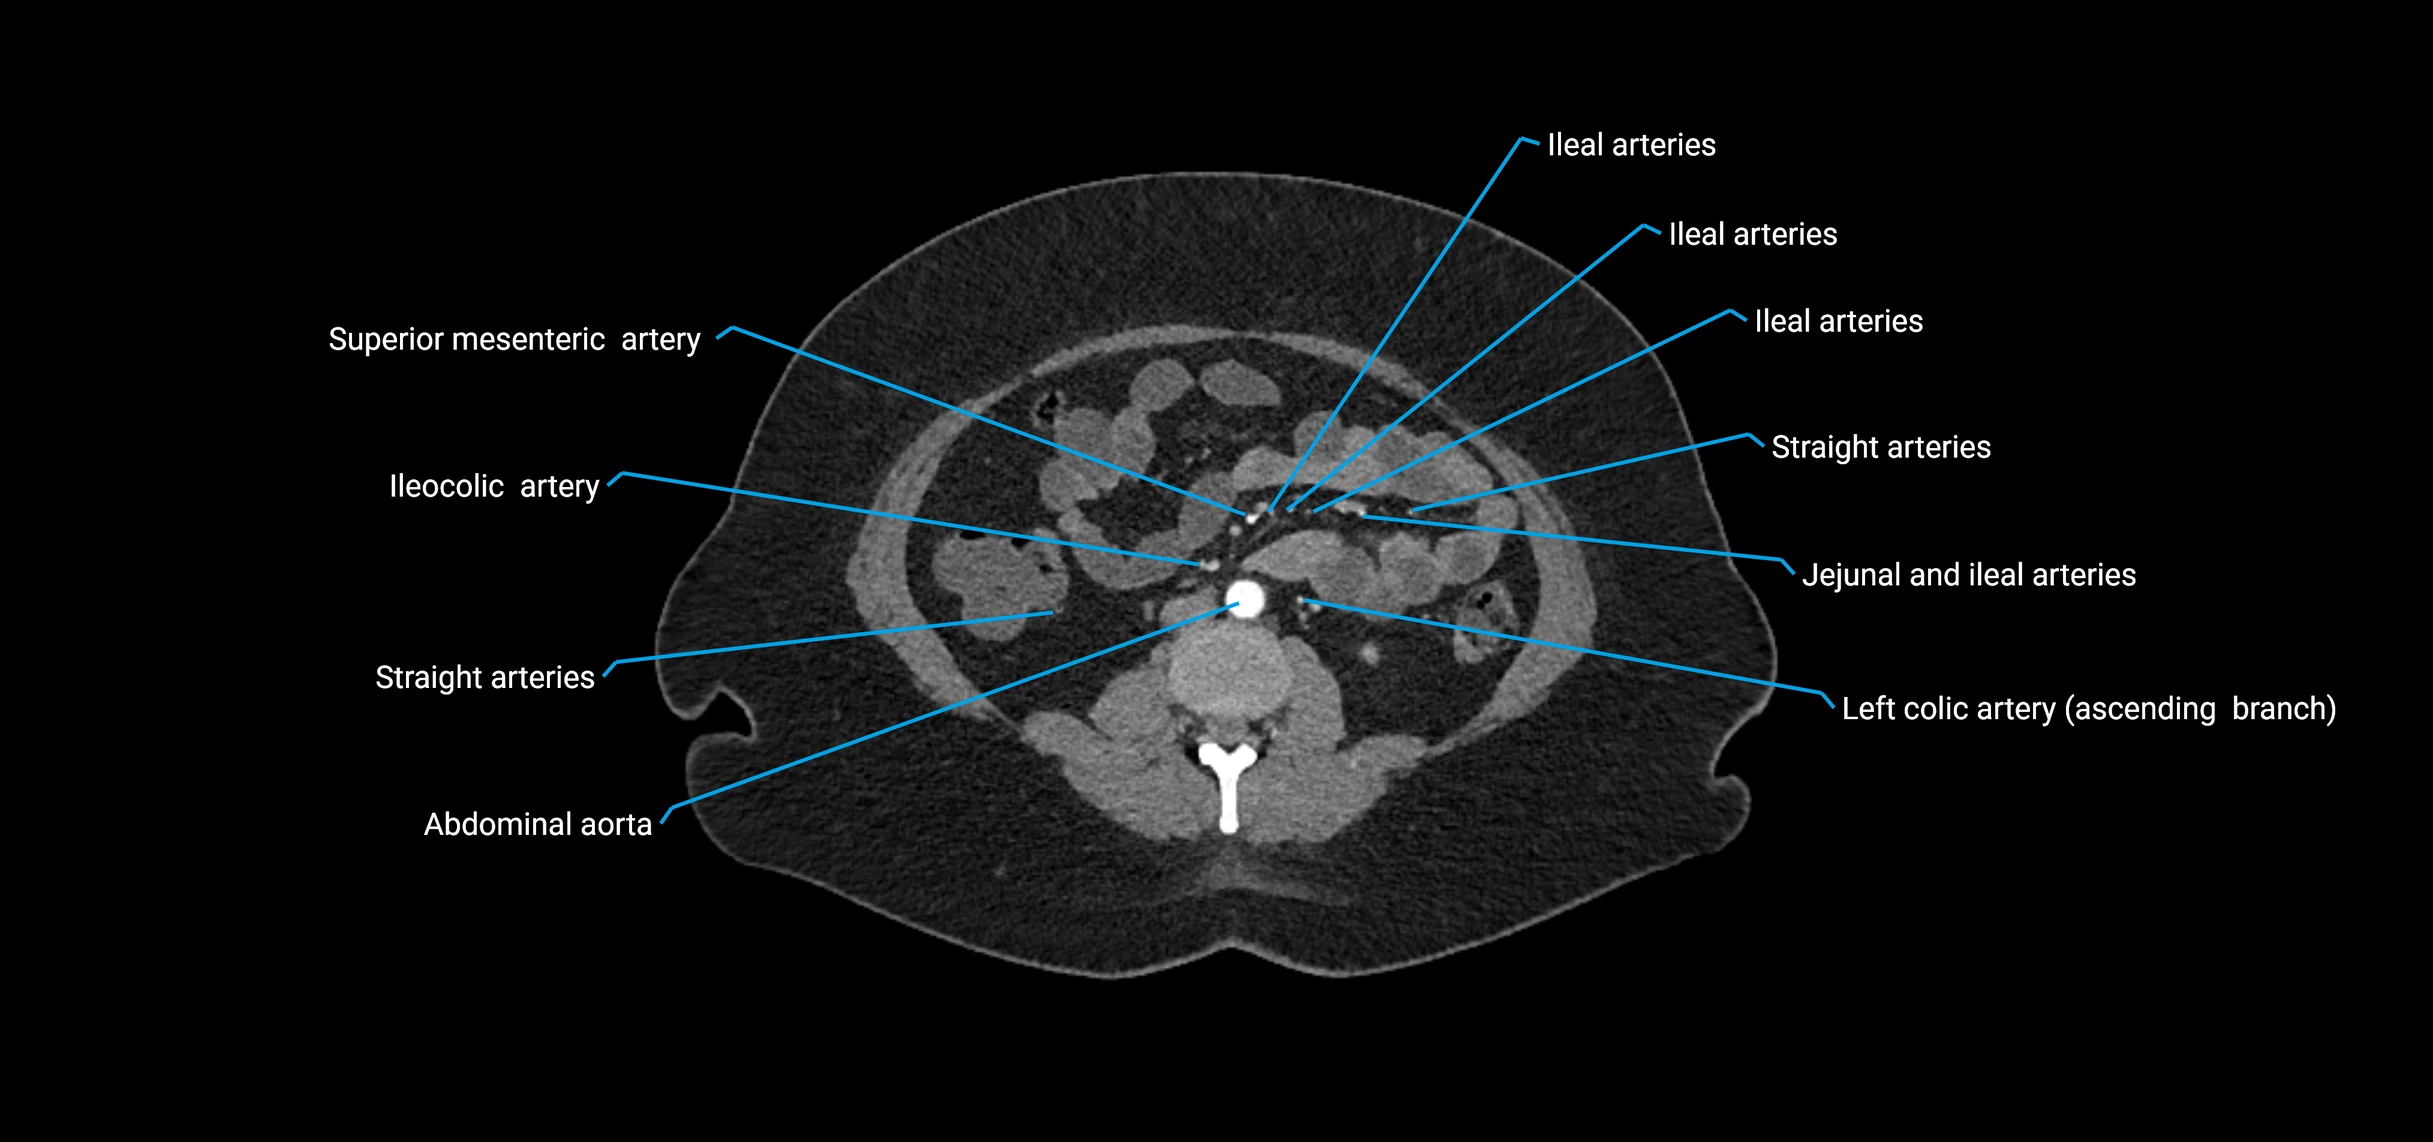

Contrast-enhanced CT (CTA):

• Gold standard for abdominal aortic imaging

• Provides excellent detail of lumen, wall, aneurysm, thrombus, and branch vessels

• Multiplanar and 3D reconstructions help in aneurysm measurement, stent graft planning, and dissection evaluation